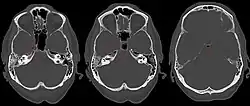

Apicitis petrosa as seen in computed tomography

In persons with longstanding ear infection and typical symptoms, medical imaging such as CT or MRI of the head may show changes that confirm disease involvement of the petrous apex of temporal bone.